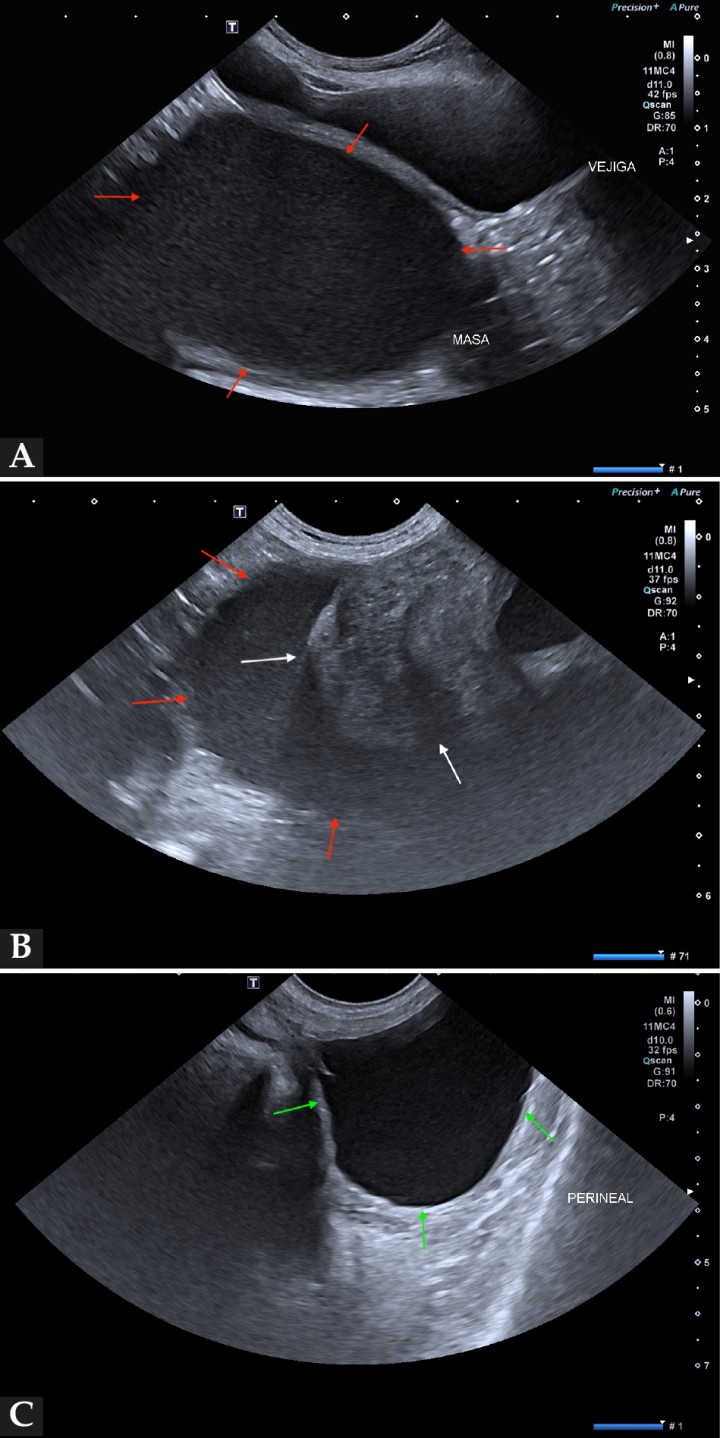

En este caso se realizó una ecografía abdominal (Fig. 3), en la que se observó una lesión cavitaria, rellena de fluido ecogénico, de dimensiones aproximadas 40 × 30 mm, caudodorsal a la vejiga de la orina, que se extendía hacia el canal pélvico y la región perineal. La lesión presentaba en su interior una estructura de paredes gruesas y heterogéneas. Además, se observó una hiperplasia quística endometrial asociada a piometra vs. mucometra vs. hidrometra, quistes ováricos bilaterales, nódulos hepáticos compatibles con hiperplasia nodular vs. neoplasia benigna vs. maligna, un colelito biliar no obstructivo y múltiples renolitos bilaterales.

<p>Ecografía abdominal en plano sagital. (<strong>A</strong>, <strong>B</strong>) Masa rellena de fluido ecogénico, dorsal a la vejiga de la orina y que se extiende hacia el canal pélvico y región perineal (flechas rojas). (<strong>B</strong>) La masa presenta paredes gruesas y heterogéneas (flechas blancas). (<strong>C</strong>) Masa rellena de fluido en la región perineal (flechas verdes).</p>

Ecografía abdominal en plano sagital. (A, B) Masa rellena de fluido ecogénico, dorsal a la vejiga de la orina y que se extiende hacia el canal pélvico y región perineal (flechas rojas). (B) La masa presenta paredes gruesas y heterogéneas (flechas blancas). (C) Masa rellena de fluido en la región perineal (flechas verdes).